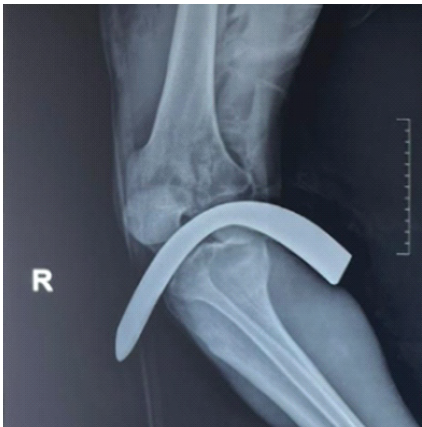

Surgical Treatment of Anchor-induced Heel Pain after Minimally Invasive Repair of Acute Achilles Tendon Rupture Using Percutaneous Achilles Repair System Achilles Midsubstance SpeedBridge™ Repair: A Case Report

David Roche , Teodor Negru , Julien Paquot , Ronny Lopes ………………………………p.122-126